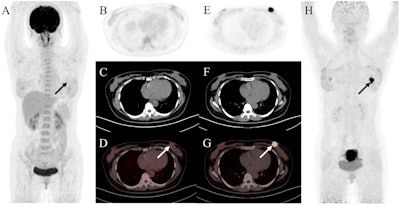

A 47-year-old woman was admitted with a left breast mass. For staging, the patient underwent F-18 FDG-PET/CT. The maximal intensity projection image (A) and the axial views (B: PET image; C: CT scan; D: PET/CT fused image) revealed normal findings. Then she underwent Ga-68 FAPI-PET/CT. The left breast showed intense uptake on Ga-68 FAPI-PET/CT (E: PET image; F: CT scan; G: PET/CT fused image; H: MIP, solid arrow; SUVmax, 15.4). Subsequently, the patient underwent pathology confirmed invasive lobular carcinoma of the left breast. Image and caption available for republishing under Creative Commons license (CC BY 4.0 DEED, Attribution 4.0 International) and courtesy of Cancer Imaging.

A 47-year-old woman was admitted with a left breast mass. For staging, the patient underwent F-18 FDG-PET/CT. The maximal intensity projection image (A) and the axial views (B: PET image; C: CT scan; D: PET/CT fused image) revealed normal findings. Then she underwent Ga-68 FAPI-PET/CT. The left breast showed intense uptake on Ga-68 FAPI-PET/CT (E: PET image; F: CT scan; G: PET/CT fused image; H: MIP, solid arrow; SUVmax, 15.4). Subsequently, the patient underwent pathology confirmed invasive lobular carcinoma of the left breast. Image and caption available for republishing under Creative Commons license (CC BY 4.0 DEED, Attribution 4.0 International) and courtesy of Cancer Imaging.